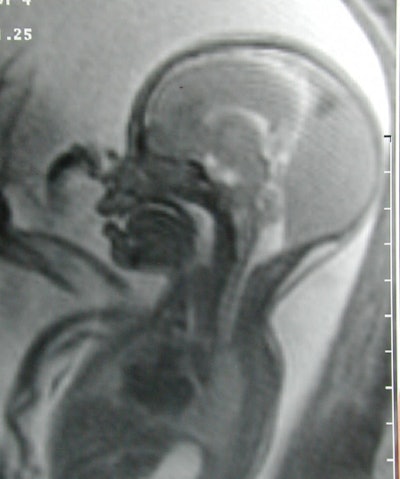

En un caso en particular, la ecografía parecía representar al cráneo del feto perforado por vasos sanguíneos -- una anomalía potencialmente mortal, explicó Dr. Carl Saphier, director de partos en Mount Sinai. Afortunadamente, al examinarlo minuciosamente con la RM, se encontró que el cráneo estaba intacto.

![]() |

un quiste con una calcificación posterior a la fosa posterior.

Imagen por gentileza de Dra. Deborah Levine.